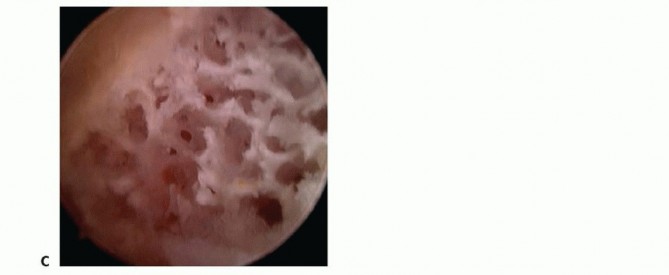

Intraoperative arthroscopic view demonstrating a central degenerative TFCC tear (Palmer Type II), characterized by frayed, unstable fibrillated margins overlying the ulnar head.

Further arthroscopic inspection reveals the extent of the degenerative perforation, exposing the chondromalacic articular surface of the distal ulna beneath the tear.